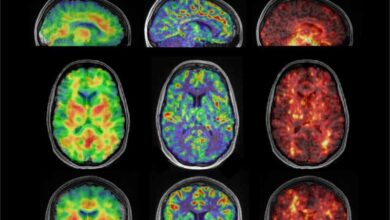

ارتباط جریان خون با سفتی مغز و خطر آلزایمر

[ad_1] ارتباط فردا: هیپوکامپ یکی از اولین نواحی در مغز است که تحت تاثیر بیماری آلزایمر قرار میگیرد؛ اختلال مغزیای…